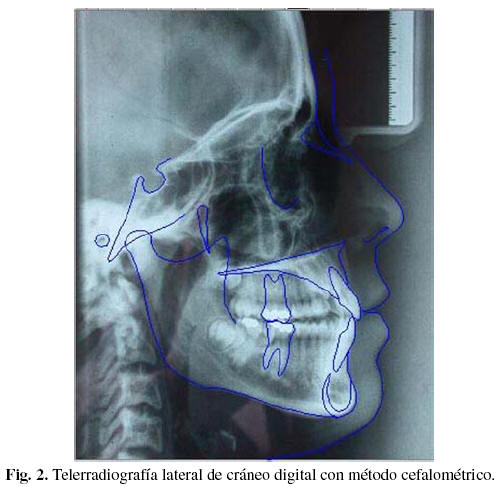

- Radiografía Lateral de Cráneo

Imagenes de distintos Análisis Radiográficos.